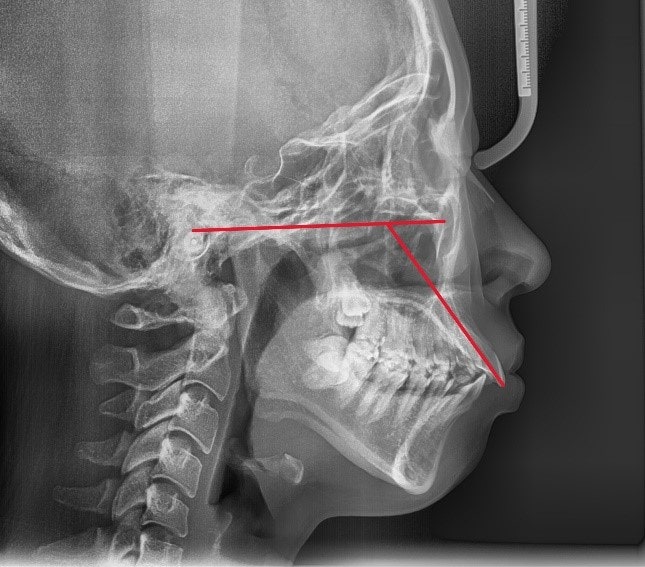

돌출입인지 아닌지를 판단하는 기준은 여러 가지가 있으나, 그 중에서 가장 간단한 방법 중 하나는 측면에서 코 끝과 턱 끝을 일직선으로 연결했을 때 입술의 위치를 평가하는 것입니다.

입술이 그 라인보다 앞쪽에 있다면 돌출입으로 판단할 수 있습니다.

돌출입의 유형은 크게 3가지로 나눌 수 있습니다.

첫째, 골격성(턱뼈 자체가 튀어나온) 돌출

둘째, 치아 각도가 뻐드러진 경우

셋째, 위 두 가지가 복합적으로 나타나는 경우

치성 돌출

서울리인치과교정과의원에서는 서울대 출신 치과교정과 전문의인 2인의 대표원장이 X-ray, 3D CT, 스캐너, AI 장비 등을 통해 환자분의 구강 상태를 정밀하게 분석하고 교차진단하고 있습니다. 이에, 한 번의 방문으로 2인의 전문의에게 정밀진단 받는 효과를 기대할 수 있으며, 중간에 주치의가 변경되는 일이 없어서 더욱 안심하고 치료를 받을 수 있습니다. 더불어 환자분이 원하는 부분과 치료적으로 필요한 부분 모두 놓치지 않도록 대표원장이 직접 1:1로 상담하여 개인에게 맞춘 치료를 적용하고 있는데요. 단순히 심미적인 개선뿐만 아니라 상하악골의 밸런스, 교합, 치아배열, 그리고 개개 치아의 각도까지 꼼꼼하게 체크하여 기능적으로도 최선의 치료를 제공할 수 있도록 노력하고 있습니다. 지금까지 돌출입 교정에 대한 내용을 말씀드렸는데요. 치아교정 특성상 오랜 기간 공들여야 하는 만큼 교정치과 선택 시 의료진의 임상경력 및 자격, 치과 장비 등을 고려하여 본인에게 꼭 맞는 치료를 받아 보시기 바랍니다. 감사합니다. |